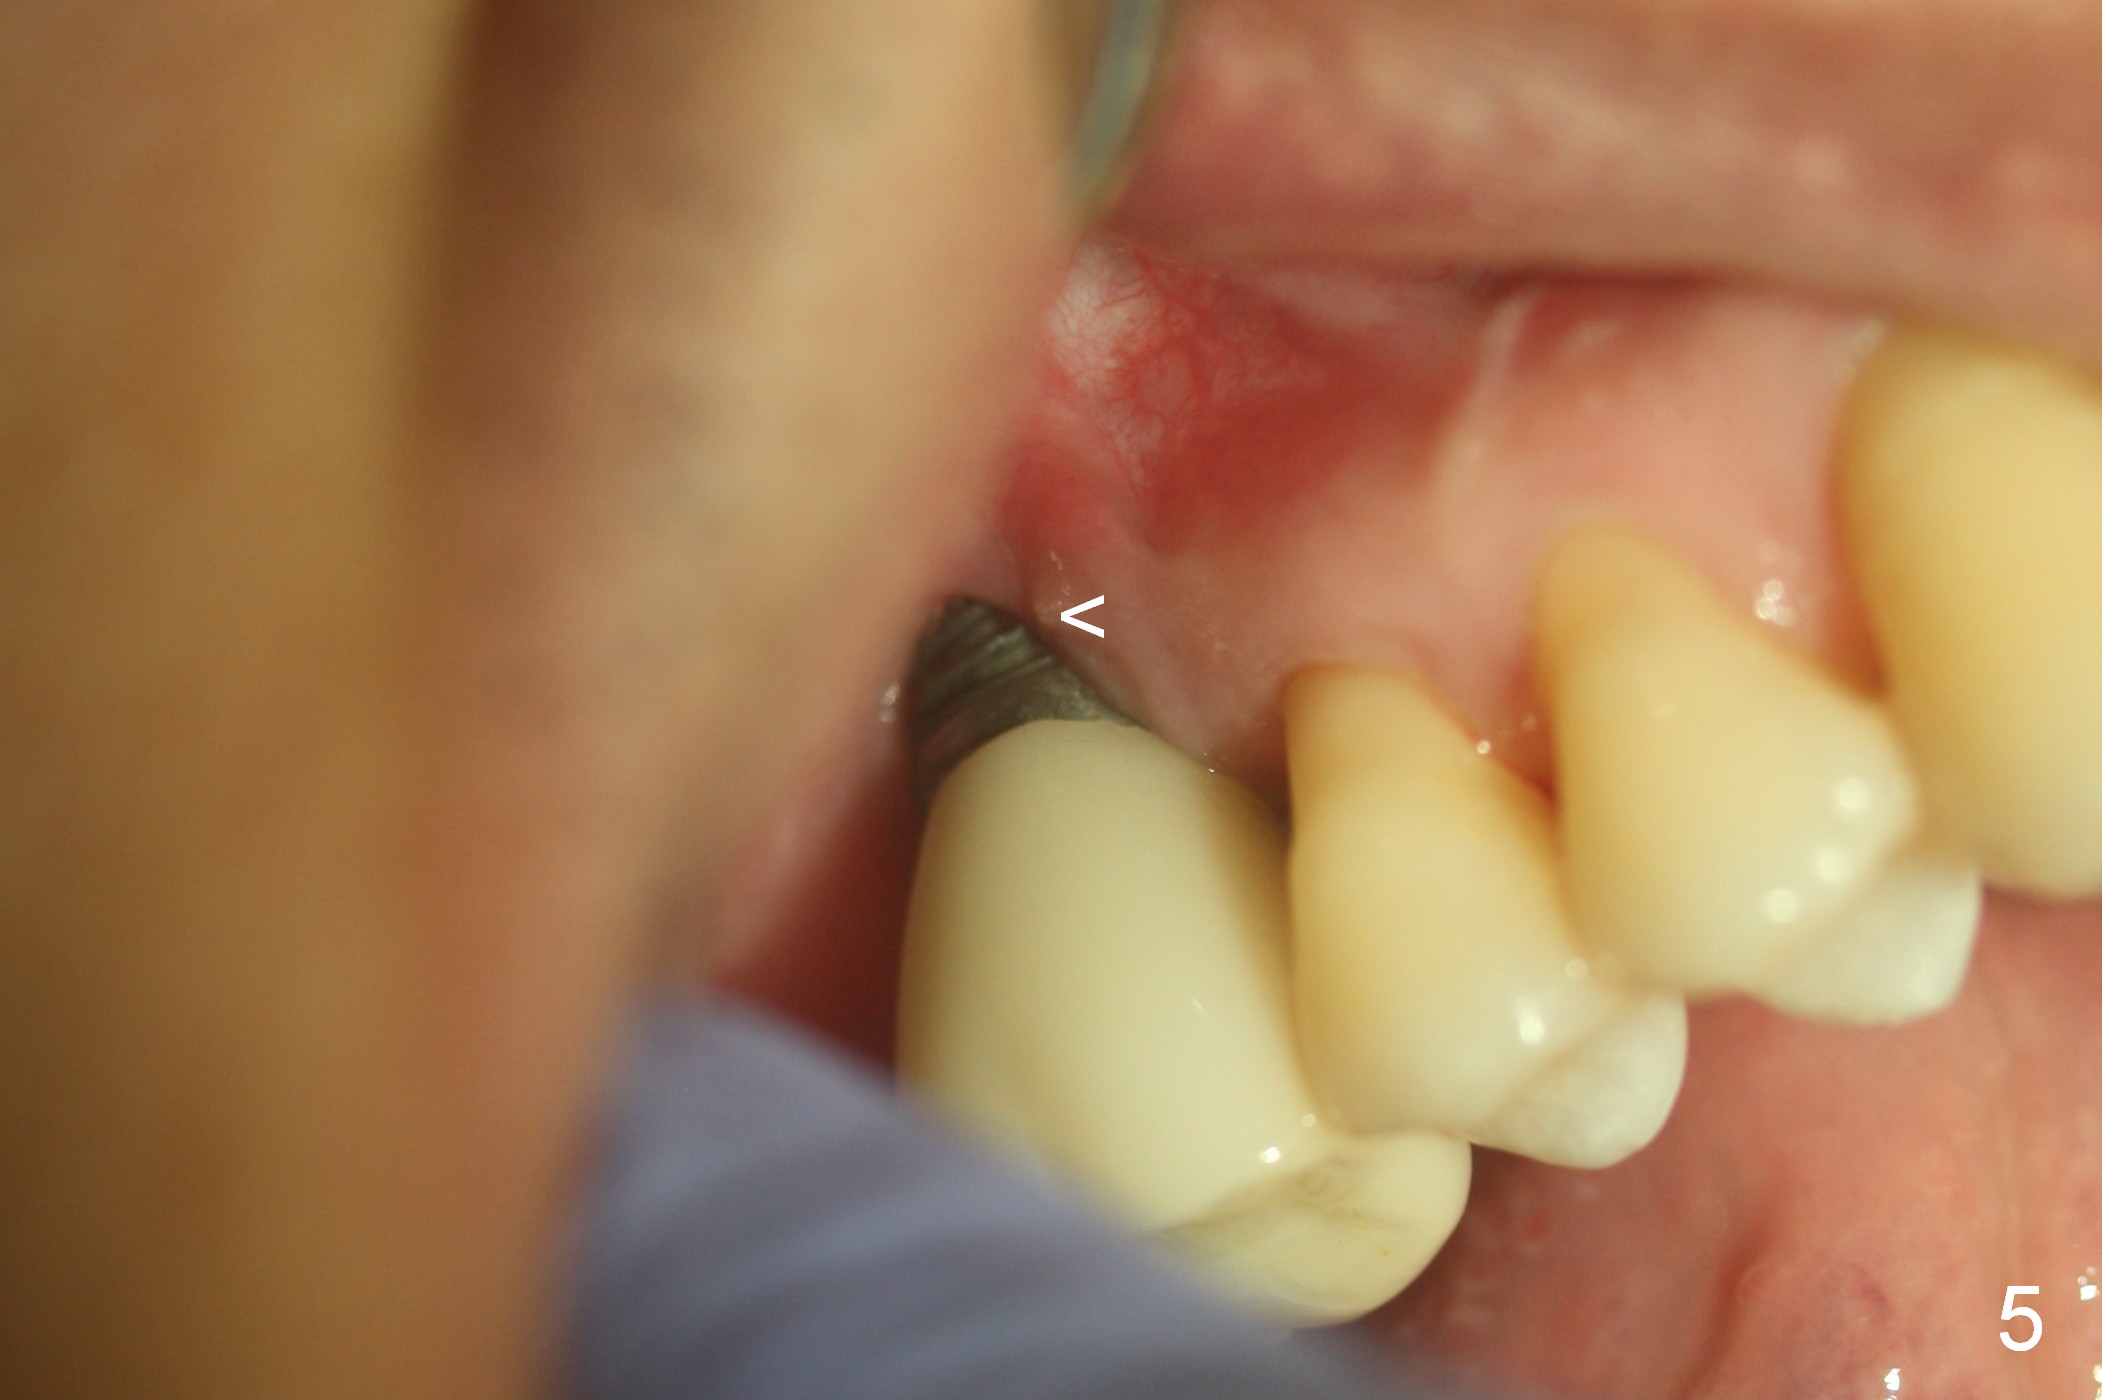

The patient returns asymptomatic for follow up 1 year post cementation. In fact the buccal threads are exposed without infection (Fig.5 <). There remains bone loss around the most coronal threads (Fig.6 *). Water pik is recommended.